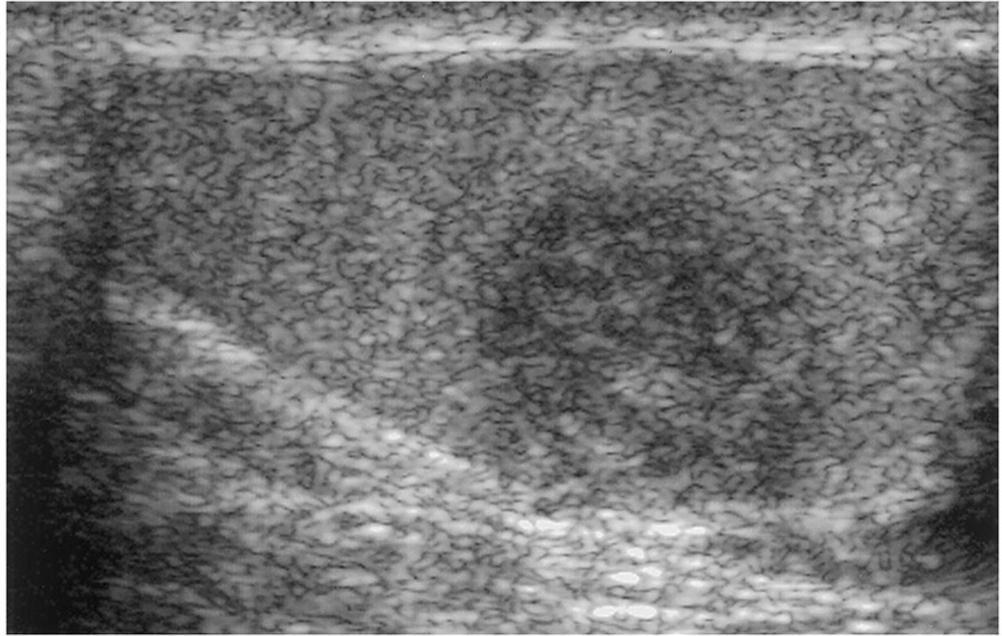

What is this?

US of the testis